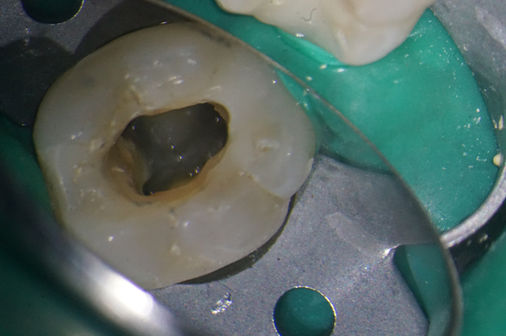

O microscópio eletrónico permite o estudo e a ampliação do sistema canalar aumentando consideravelmente a taxa de sucesso deste tratamento, sendo possível desinfetar e preencher, de forma previsível, áreas que não seriam visíveis para o médico dentista sem o recurso à ampliação. Possibilitando também a localização de canais calcificados e de pequenas dimensões preservando mais estrutura dentária, a remoção de instrumentos fraturados dentro do sistema canalar, a reparação de perfurações, entre outros.

Com recurso a um dos mais recentes modelos de microscópio eletrónico disponível no mercado, a consulta de endodontia da NCB, permite registar através de imagens e/ou vídeo o tratamento realizado para que o paciente possa acompanhar todo o desenvolvimento do mesmo.